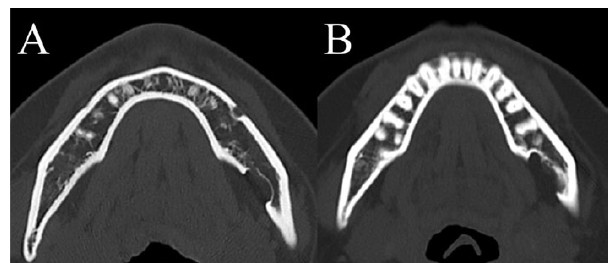

Case Report: A 36-year-old female diagnosed SBC for 10 years ago, accidentally by radiographic study. The cavity of bone defect has been enlarged gradually without any symptoms. Computed tomography (CT) showed the oval-shaped depression 20 mm × 13 mm × 8 mm in size at the left mandibular area. Magnetic resonance imaging (MRI) showed no tumor-like components in the cavity. Computed tomography angiography revealed the submental artery from the facial artery runs around the cavity. These radiographical findings presumed that localized pulsative pressure by the submental artery had formed SBC. Because of progressive enlargement of bone cavity in young female, it was afraid that mandibular bone fracture would be brought in later. To prevent the increment of bone deficit, the endovascular intervention had been performed. The submental artery was embolized by glue. Then, the growth of SBC has been suppressed after the endovascular intervention.